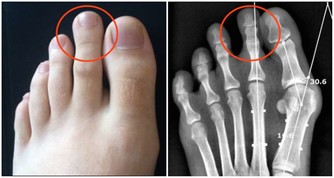

肚臍與身體的連接結構